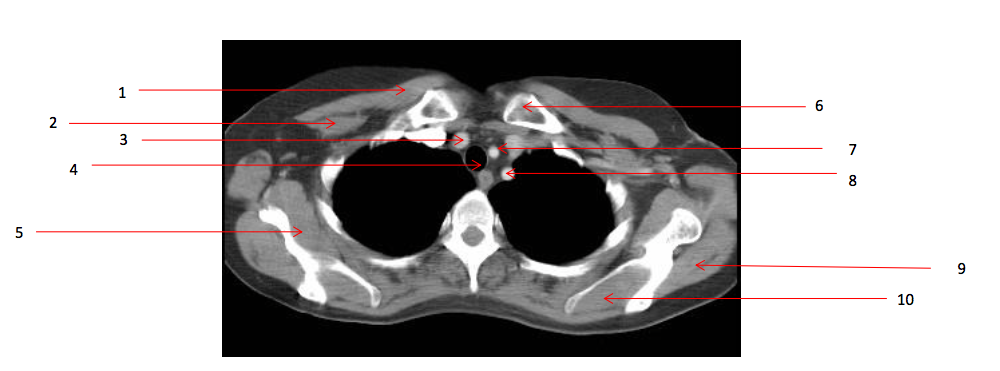

1

Number 2?

Rt pectoralis minor muscle

Number 6?

Lt clavicle

3

Number 10?

4

Number 1?

5

Number 8?

Lt subclavian artery

6

Number 4?

Trachea

7

Number 7?

Lt common carotid artery

8

Number 19?

9

Number 5?

Rt subscapularis muscle

10

Number 13?

Rt erectae spinae muscle

11

Number 9?

Lt infraspinatus muscle

13

Number 16?

Lt scapula

15

Number 14?

Lt brachiocephalic vein

16

Number 17?

SVC

17

Number 11?

Sternum (manubrium)

18

Number 20?

Ascending aorta

20

Number 12?

Rt brachiocephalic vein

Q

Number 3?

A

Brachiocephalic artery

43

Number 15?

oesophagus